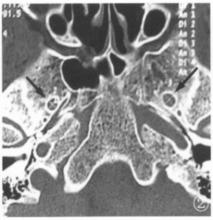

圖1 卵圓孔為圓形、兩側對稱根據結果分析,CT觀測國人卵圓孔形態多樣,但以橢圓形為多見,占67.81%,腎形、梨形、長條形、圓形分別占6.10%、9.02%、9.02%、8.05%。陳盛剛 報導顱骨標本測量卵圓孔形態橢圓形占80%比本組高,這可能與我們將卵圓孔內側緣較短、外側緣較長的另列為梨形有關,而與何玉泉 等報導顱骨標本測量卵圓孔形態橢圓形占69.87%相仿。多數個體卵圓孔兩側對稱、形態相同(占65.7%)(圖1)。但兩側形態不一,呈非對稱的也不少(占34.3%)(圖2)。在臨床影像診斷作雙側形態照時應引起注意。特別是長條形的卵圓孔寬徑小,占8.05%。較何玉泉等報導的要高。在經卵圓孔射頻治療三叉神經痛時較困難,更要注意。為此,在經卵圓孔射頻治療三叉神經痛前,必須先行顱底卵圓孔CT掃描,確定卵圓孔的形態、大小,可以估計穿刺的難易及效果。